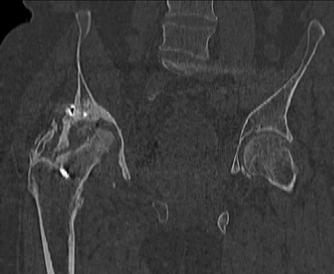

Пациент 49 лет, паровозная травма 23.2.2006, получил вертикальная

нестабильное повреждение таза, разрыв левого крестцово-подвздошного

сочленения, перелом лонной, седалищной костей слева, T-образный

оскольчатый перелом правой вертлужной впадины с переломом заднего

края, вывих правого бедра, посттравматическая пояснично-крестцовая

плексопатия с обеих сторон, паралич мышц правой голени.

В день травмы - вправление вывиха, скелетное вытяжение, 14.3.2006

чрескостный остеосинтез таза. 20.4.2006 остеосинтез правой вертлужной

впадины пластинами, осложнившийся нагноением межмышечной гематомы

правой ягодичной области. Получал консервативное лечение, было

достигнуто полное заживление раны. 24.7.2006 введены илиосакральные

винты слева. С декабря 2006 года и по настоящее время ходит на

костылях без опоры на правую ногу. Планируется THA. Помогите

определиться с вариантом костной пластики? И какую укрепляющую

конструкцию использовать?